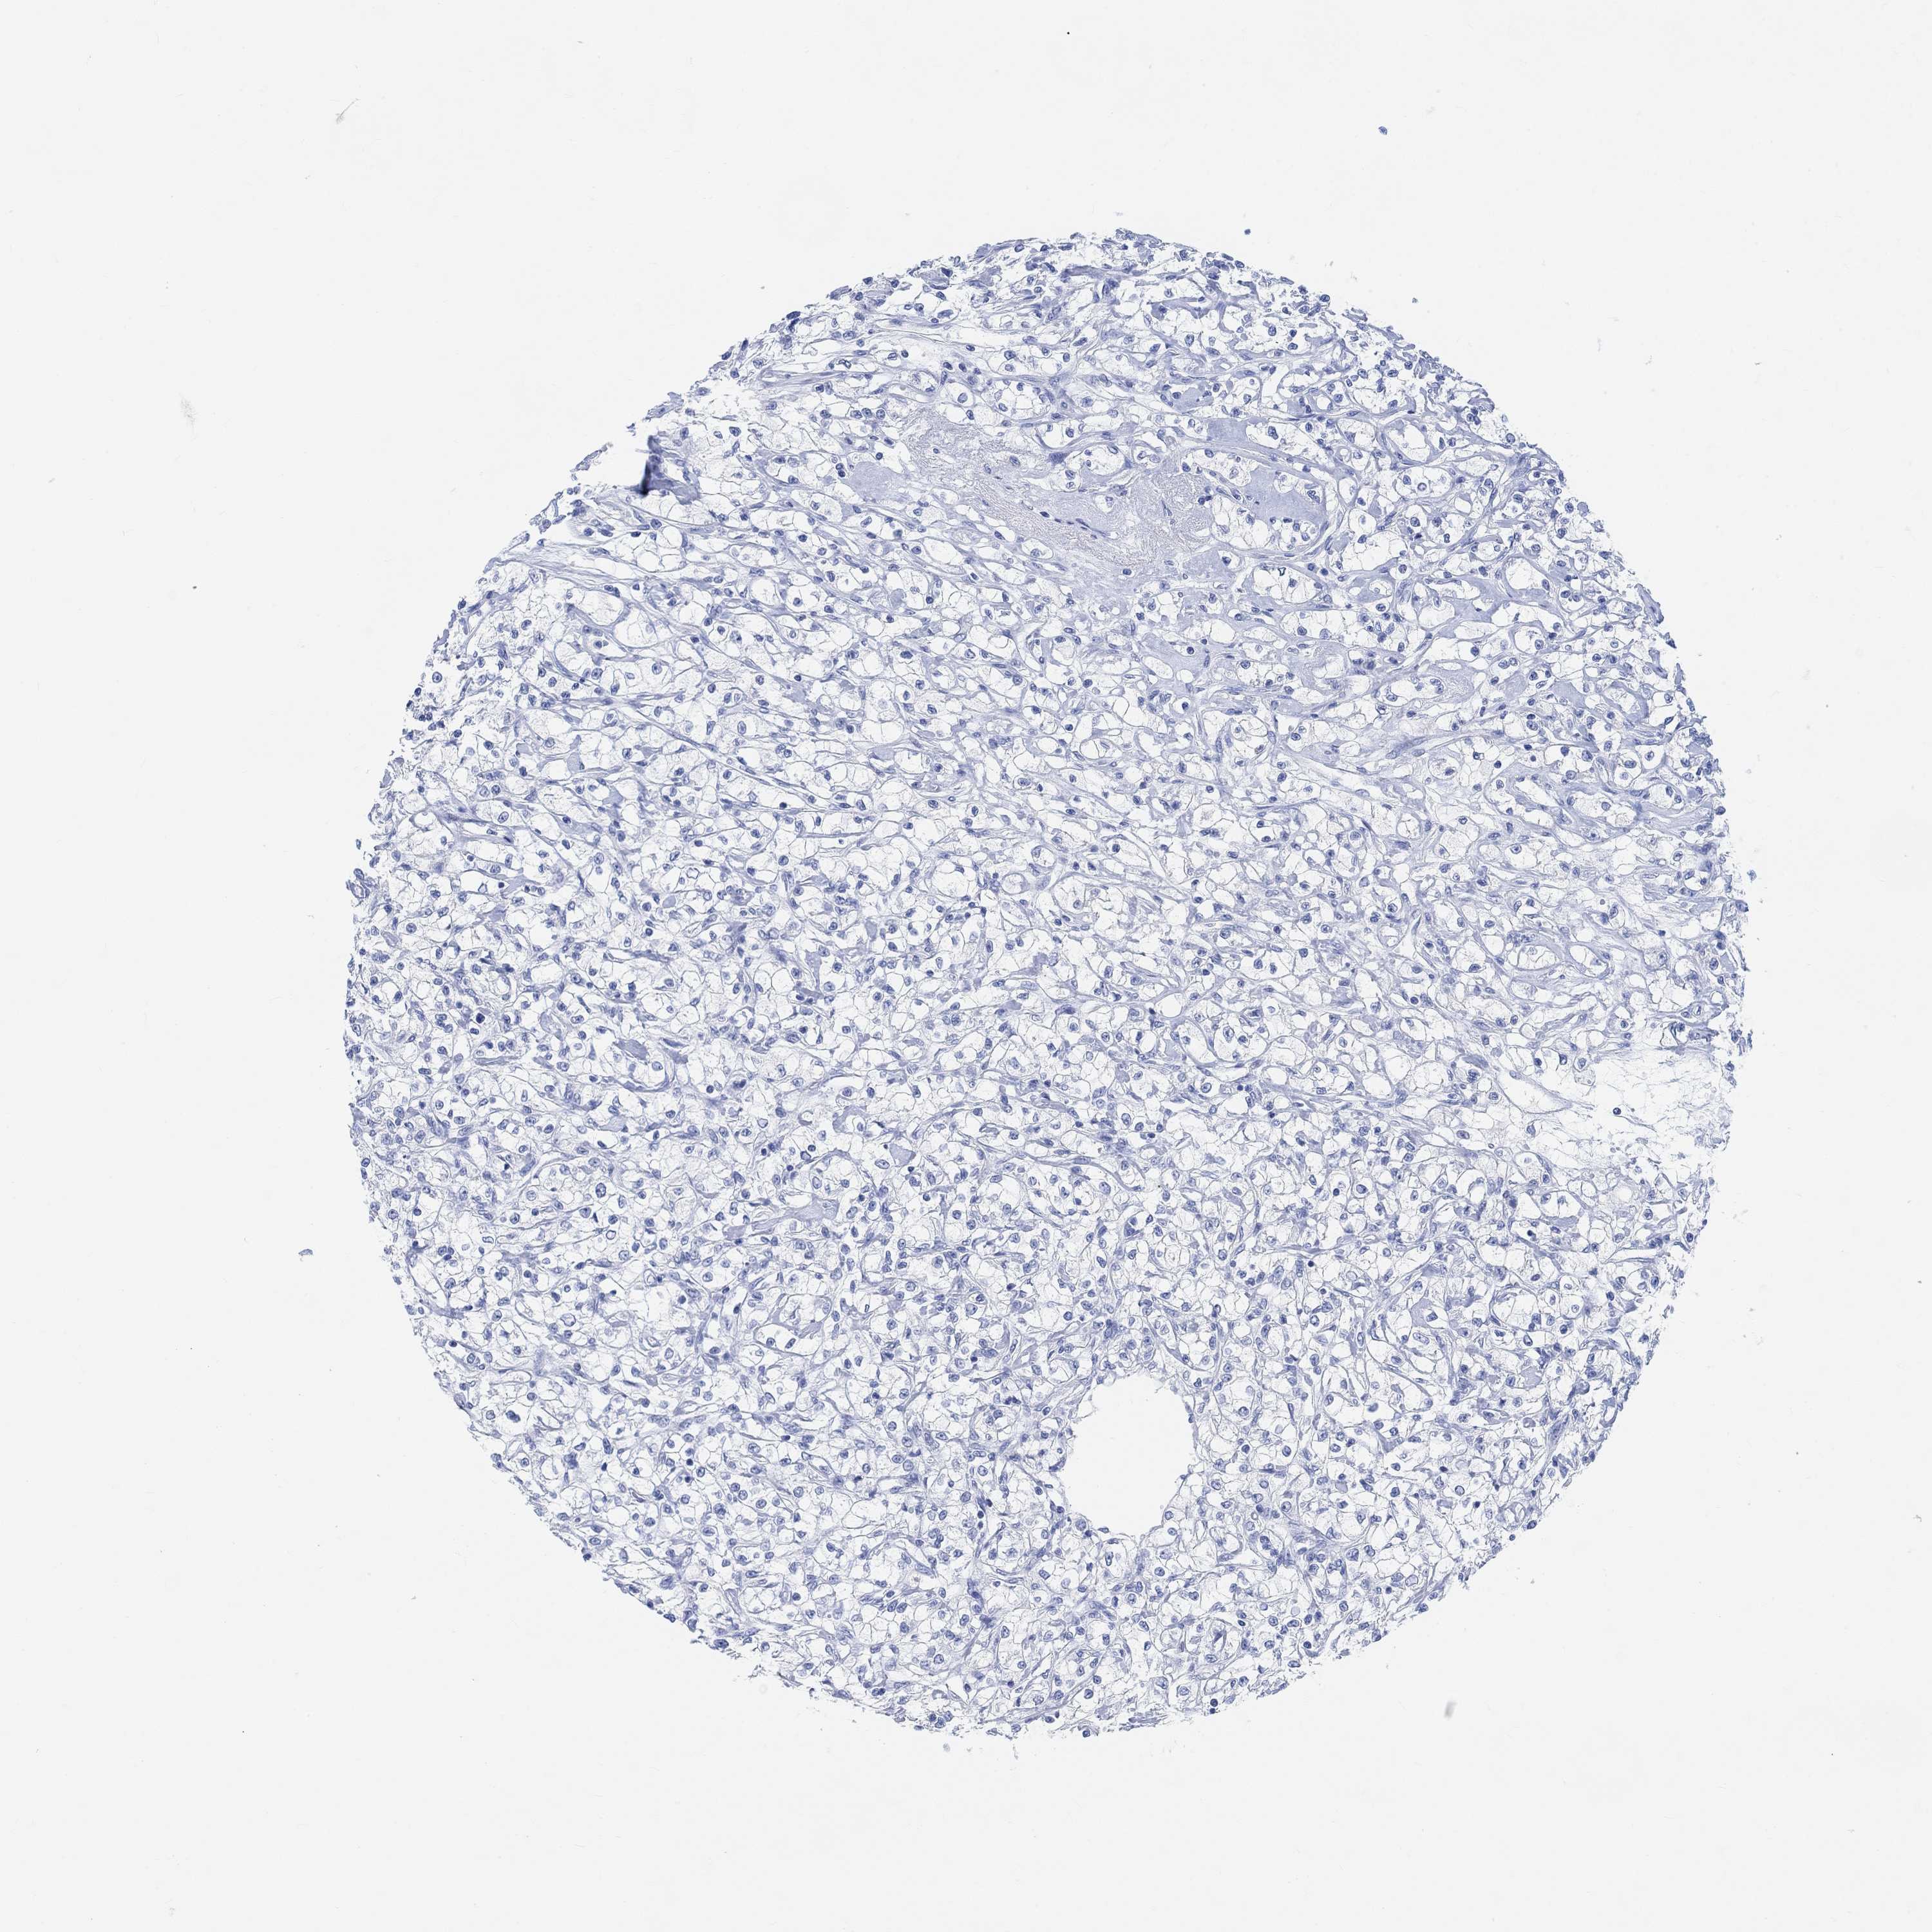

CANCER RENAL CANCER Show tissue menu

KICH TCGA KIRC TCGA KIRC VALIDATION KIRP TCGA PROTEIN RCC CPTAC PROTEIN EXPRESSION